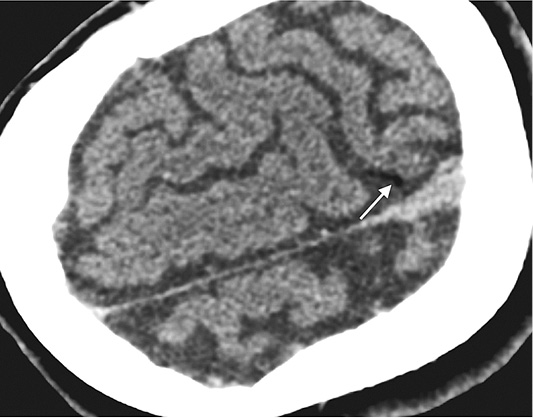

62-year-old female with smoking history of 35 pack years was referred to interventional radiology department for a biopsy of the right lung lesion. The lesion was found accidentally during CT investigation before planed aortocoronary bypass surgery. At 6-month follow-up the subsolid lesion remained stable while its suspicious appearance as subsolid nodule with ground glass area at its periphery indicated to perform a biopsy (Figure 1).

Figure 1. Subsolid lesion of the right lung (red arrow) – suspicious for malignancy. This lesion was the target for lung biopsy. Two additional calcified lesions bilaterally (blue arrows) – most probably related to tuberculosis infection 20 years ago.